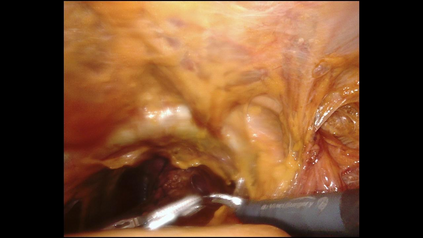

Endoscopic video recordings are widely used in minimally invasive robot-assisted surgery, but when the endoscope is outside the patient's body, it can capture irrelevant segments that may contain sensitive information. To address this, we propose a framework that accurately detects out-of-body frames in surgical videos by leveraging self-supervision with minimal data labels. We use a massive amount of unlabeled endoscopic images to learn meaningful representations in a self-supervised manner. Our approach, which involves pre-training on an auxiliary task and fine-tuning with limited supervision, outperforms previous methods for detecting out-of-body frames in surgical videos captured from da Vinci X and Xi surgical systems. The average F1 scores range from 96.00 to 98.02. Remarkably, using only 5% of the training labels, our approach still maintains an average F1 score performance above 97, outperforming fully-supervised methods with 95% fewer labels. These results demonstrate the potential of our framework to facilitate the safe handling of surgical video recordings and enhance data privacy protection in minimally invasive surgery.